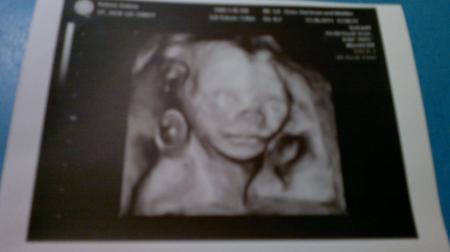

hallo ihr lieben ich hatte ja gestern mein FD termin und mein freund war auch das erste mal mit bei. Den baby geht es gut und alles zeitgerecht entwickelt :) und der arzt hat uns auch alles super erklärt . der ultraschall hat ungefähr 1 stunde gedauert und es war so schön mein baby so lange zu sehen . Wir haben so gar ein Bild von gesicht bekommen das hab ich unten für euch rangehangen . Und jetzt kommen wir zum geschlecht wenn der arzt wirklich richtig geguckt hat dann . . . . . . . . . . wird es ein Mädchen . ich hab mich über das outing sehr gefreut aber mein freund überhaupt nicht, weil er ein jungen haben wollte er war sehr sauer :( aber ich kann ja dafür auch nix

Super Bild, herzlichen Glückwunsch ach der Papa gewöhnt sich schnell an die kleine Prinzessin :) ich freu mich mit Euch.

Guten Morgen, na herzlichen Glückwunsch zum Mädchen, so langsam kommen ja doch auch mal mehr Mädchenoutings. Ach und dein Freund fängt sich auch wieder Und echt tolles Bild hast du bekommen. lg p.s. heute in die 23.Woche gerutscht juhuuu

Herzlichen Glückwunsch und... Wow, sehr klares und schönes Foto :) Lg Jasmin

Herzlichen Glückwunsch zu Mädchen, wir bekommen auch eins unser zweites.. Mein Männe war auch erst einwenig traurig, weil er hatte doch auf einen Jungen gehofft wegen dem Geschlechterausgleich,lach. Aber mitlerweile freut er sich total. Nur die Namenssuche ist ne Qual,grins. Liebe Grüße an deinen Freund, für das Geschlecht ist er ganz alleine für zuständig, da haben wir Frauen kein mitspracherecht,lach.. Schön das alles i.O. ist und das ihr euer Baby solange beobachtet konntet. Das Bild ist wirklich gut geworden.. LG Jeannett